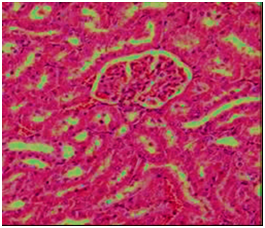

The histopathological study

The biochemical results were confirmed by the histological examination in liver and kidney tissues. The histological examination of the structure of liver in the control group was normal hepatocytes and central (Figure 3). Liver of rats in group four that fed AFB1-contaminant diet (2.5 mg/kg feed) alone showed enlarged portal area and dilated thick wall portal vein and also appeared accumulation of cellular infiltration and fibrous tissues around proliferated bile ducts thick (arrow) (Figure 4). Rats fed on AFB1 free diet and treated with ozone showed the hepatic cells and central vein are nearly normal (Figure 5). In the other hand, animal in group fed AFB1-contaminated diet after ozonation at 20 and/or40 ppm ozone gas showed the area around the central vein is nearly normal and nearly normal hepatocytes and the damaged area around the portal tracts is not noticed (Figure 6). The liver is the main target organ for AFs and chronic exposure to low levels in foodstuffs cause liver fibrosis and primary liver cancer.29 Microscopic examination of kidney section of control rats showed the normal structure of renal tissue in convoluted tubules and the Bowman capsule (Figure 7). But rats fed AFB1-contaminant diet alon showed distal tubules have fatty degeneration and eosinophilic cytoplasm as well as pyknotic nuclei. Interstatial edema and inflammation also present (Figure 8). While rats fed on AFB1 free diet and treated with ozone showed the nearly normal structural of renal tissue and normal convoluted tubules and the Bowman capsule also rats fed AFB1-contaminated diet after ozonation (Figure 9 & Figure 10). In the current study, animals’ fedAFB1 free diet after ozonation (ozone gas treated wheat alone) did not show any significant effects however, when the AFB1-contaminated wheat grain after ozonation, a significant improvement was observed in the serum biochemical parameters tested and histological examination in liver and kidney tissues. This could be due to the AFB1 been degraded after ozone treatment of the contaminated wheat. These results were in agreement with.22 The primary reaction site of ozone in AFB1 and is the C8-C9 double bond at the terminal furan. This site has been associated with AFB1 toxicity, mutagenicity, and carcinogenic.5 This reaction resulted in the formation of aflatoxinmolozonide which is further change to aflatoxinozonide. This compound is unstable and change to aldehydes, Ketones, acids and CO2 (Figure 11). Ozone is a decomposes to form oxygen gas and therefore can be classified as a no persistent chemical; however, it must be generated at the location of its intended use

Figure 9 Section in kidney of group fed on AFB1 free diet and treated with ozone gas showing nearly normal convoluted tubules and the Bowman corpuscle   (H &E 200).

Figure 10 Section in kidney of rat fed AFB1-contaminated diet after ozonation showing significant improvements in liver tissues and normal hepatocytes (H&E 200).